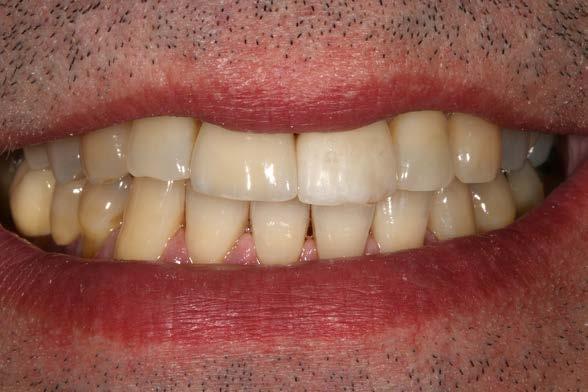

ya cicatrización parcial del tejido blando. Estando en esta fase de cicatrización temprana, podemos además adaptar los tejidos blandos a la emergencia que queremos darle al incisivo central (Figura 12 y 13 ). La prótesis provisional se mantiene durante 3 meses. Transcurrido este tiempo se confecciona sobre el mismo transepitelial la prótesis definitiva. De esta manera, las uniones epiteliales formadas entre el tejido gingival periimplantario y el transepitelial no se rompen, garantizándose un mejor sellado a este nivel, evitándose problemas como la mucositis periimplantaria. El paciente continúa en seguimiento posterior durante 2 años. En las imágenes clínicas se observa la estabilidad de los tejidos blandos (Figura 14 y 15). En este momento del seguimiento se realiza un nuevo cone-beam en el que vemos la anchura lograda a nivel crestal, con una regeneración completa de la tabla vestibular (Figura 16).

el mismo transepitelial, realizando una prótesis provisional sobre interfase (del mismo modo que si fuese definitiva) sin romper la unión implante-tejido blando en la zona crítica ha podido marcar la diferencia en cuanto a la conservación del tejido blando periimplantario y, por lo tanto, también del hueso crestal adyacente. El manejo del gap es otro punto diferencial en el éxito a largo plazo del implante inmediato, como

hemos explicado anteriormente. En nuestro caso, el uso de PRGF-Endoret para rellenarlo ha generado un hueso estable, como hemos podido evidenciar en el tac de control a los 2 años, así como evitar la reabsorción de la tabla vestibular, hecho clave en la zona estética. Existen numerosas referencias en la literatura internacional en los que se ha puesto a prueba el potencial del PRGF-Endoret como regenerador del alveolo

Figuras 14 y 15. Estado de los tejidos blandos 2 años después de la colocación de la prótesis definitiva.

Figura 16. Comparativa inicial y final a los 2 años del seguimiento con la regeneración completa de la tabla vestibular y el mantenimiento tras la carga.

postextracción se ha evidenciado su buen comportamiento obteniendo resultados de regeneración de tejido óseo y tejido blando superiores a muchos materiales empleados habitualmente o frente a la regeneración a través de coágulo sanguíneo (técnica convencional).19-24

Conclusiones

La técnica del implante postextracción inmediata debe ser empleada en aquellos casos en los que tras un análisis exhaustivo del caso las características permitan obtener un resultado estable a largo plazo. La valoración de la posición del implante y el sellado del gap en los casos en los que sea necesario deben ser tenidos en cuenta a la hora de desarrollar el protocolo quirúrgico. El PRGF-Endoret puede ser utilizado para el sellado del gap como material único, tal como hemos visto en este caso, aunque dependerá de la extensión del mismo el que decidamos unir otros materiales como el hueso autólogo.